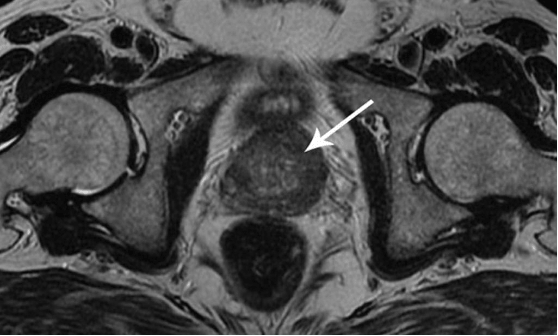

Evo kako izgleda upala prostate uzrokovana stagnacijom sperme (kada se testisi ne prazne). Trajna upala dovodi do adenoma prostate, a kasnije do raka prostate (prema statistikama, 38% muškaraca umire zbog ovoga). Zbog odsustva seksa, ovo se dešava uvek i to je razlog zašto se adenom prostate naziva "bolešću starih".